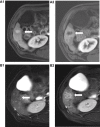

Hepatocellular carcinoma (HCC) is one of the most common tumors worldwide, usually occurring on a background of liver cirrhosis. HCC is a highly vascular tumor in which angiogenesis plays a major role in tumor growth and spread. Tumor-induced angiogenesis is usually related to a complex interplay between multiple factors and pathways, with vascular endothelial growth factor being a major player in angiogenesis. In the past decade, understanding of tumor-induced angiogenesis has led to the emergence of novel anti-angiogenic therapies, which act by reducing neo-angiogenesis, and improving patient survival. Currently, Sorafenib and Lenvatinib are being used as the first-line treatment for advanced unresectable HCC. However, a disadvantage of these agents is the presence of numerous side effects. A major challenge in the management of HCC patients being treated with anti-angiogenic therapy is effective monitoring of treatment response, which decides whether to continue treatment or to seek second-line treatment. Several criteria can be used to assess response to treatment, such as quantitative perfusion on cross-sectional imaging and novel/emerging MRI techniques, including a host of known and emerging biomarkers and radiogenomics. This review addresses the pathophysiology of angiogenesis in HCC, accurate imaging assessment of angiogenesis, monitoring effects of anti-angiogenic therapy to guide future treatment and assessing prognosis.